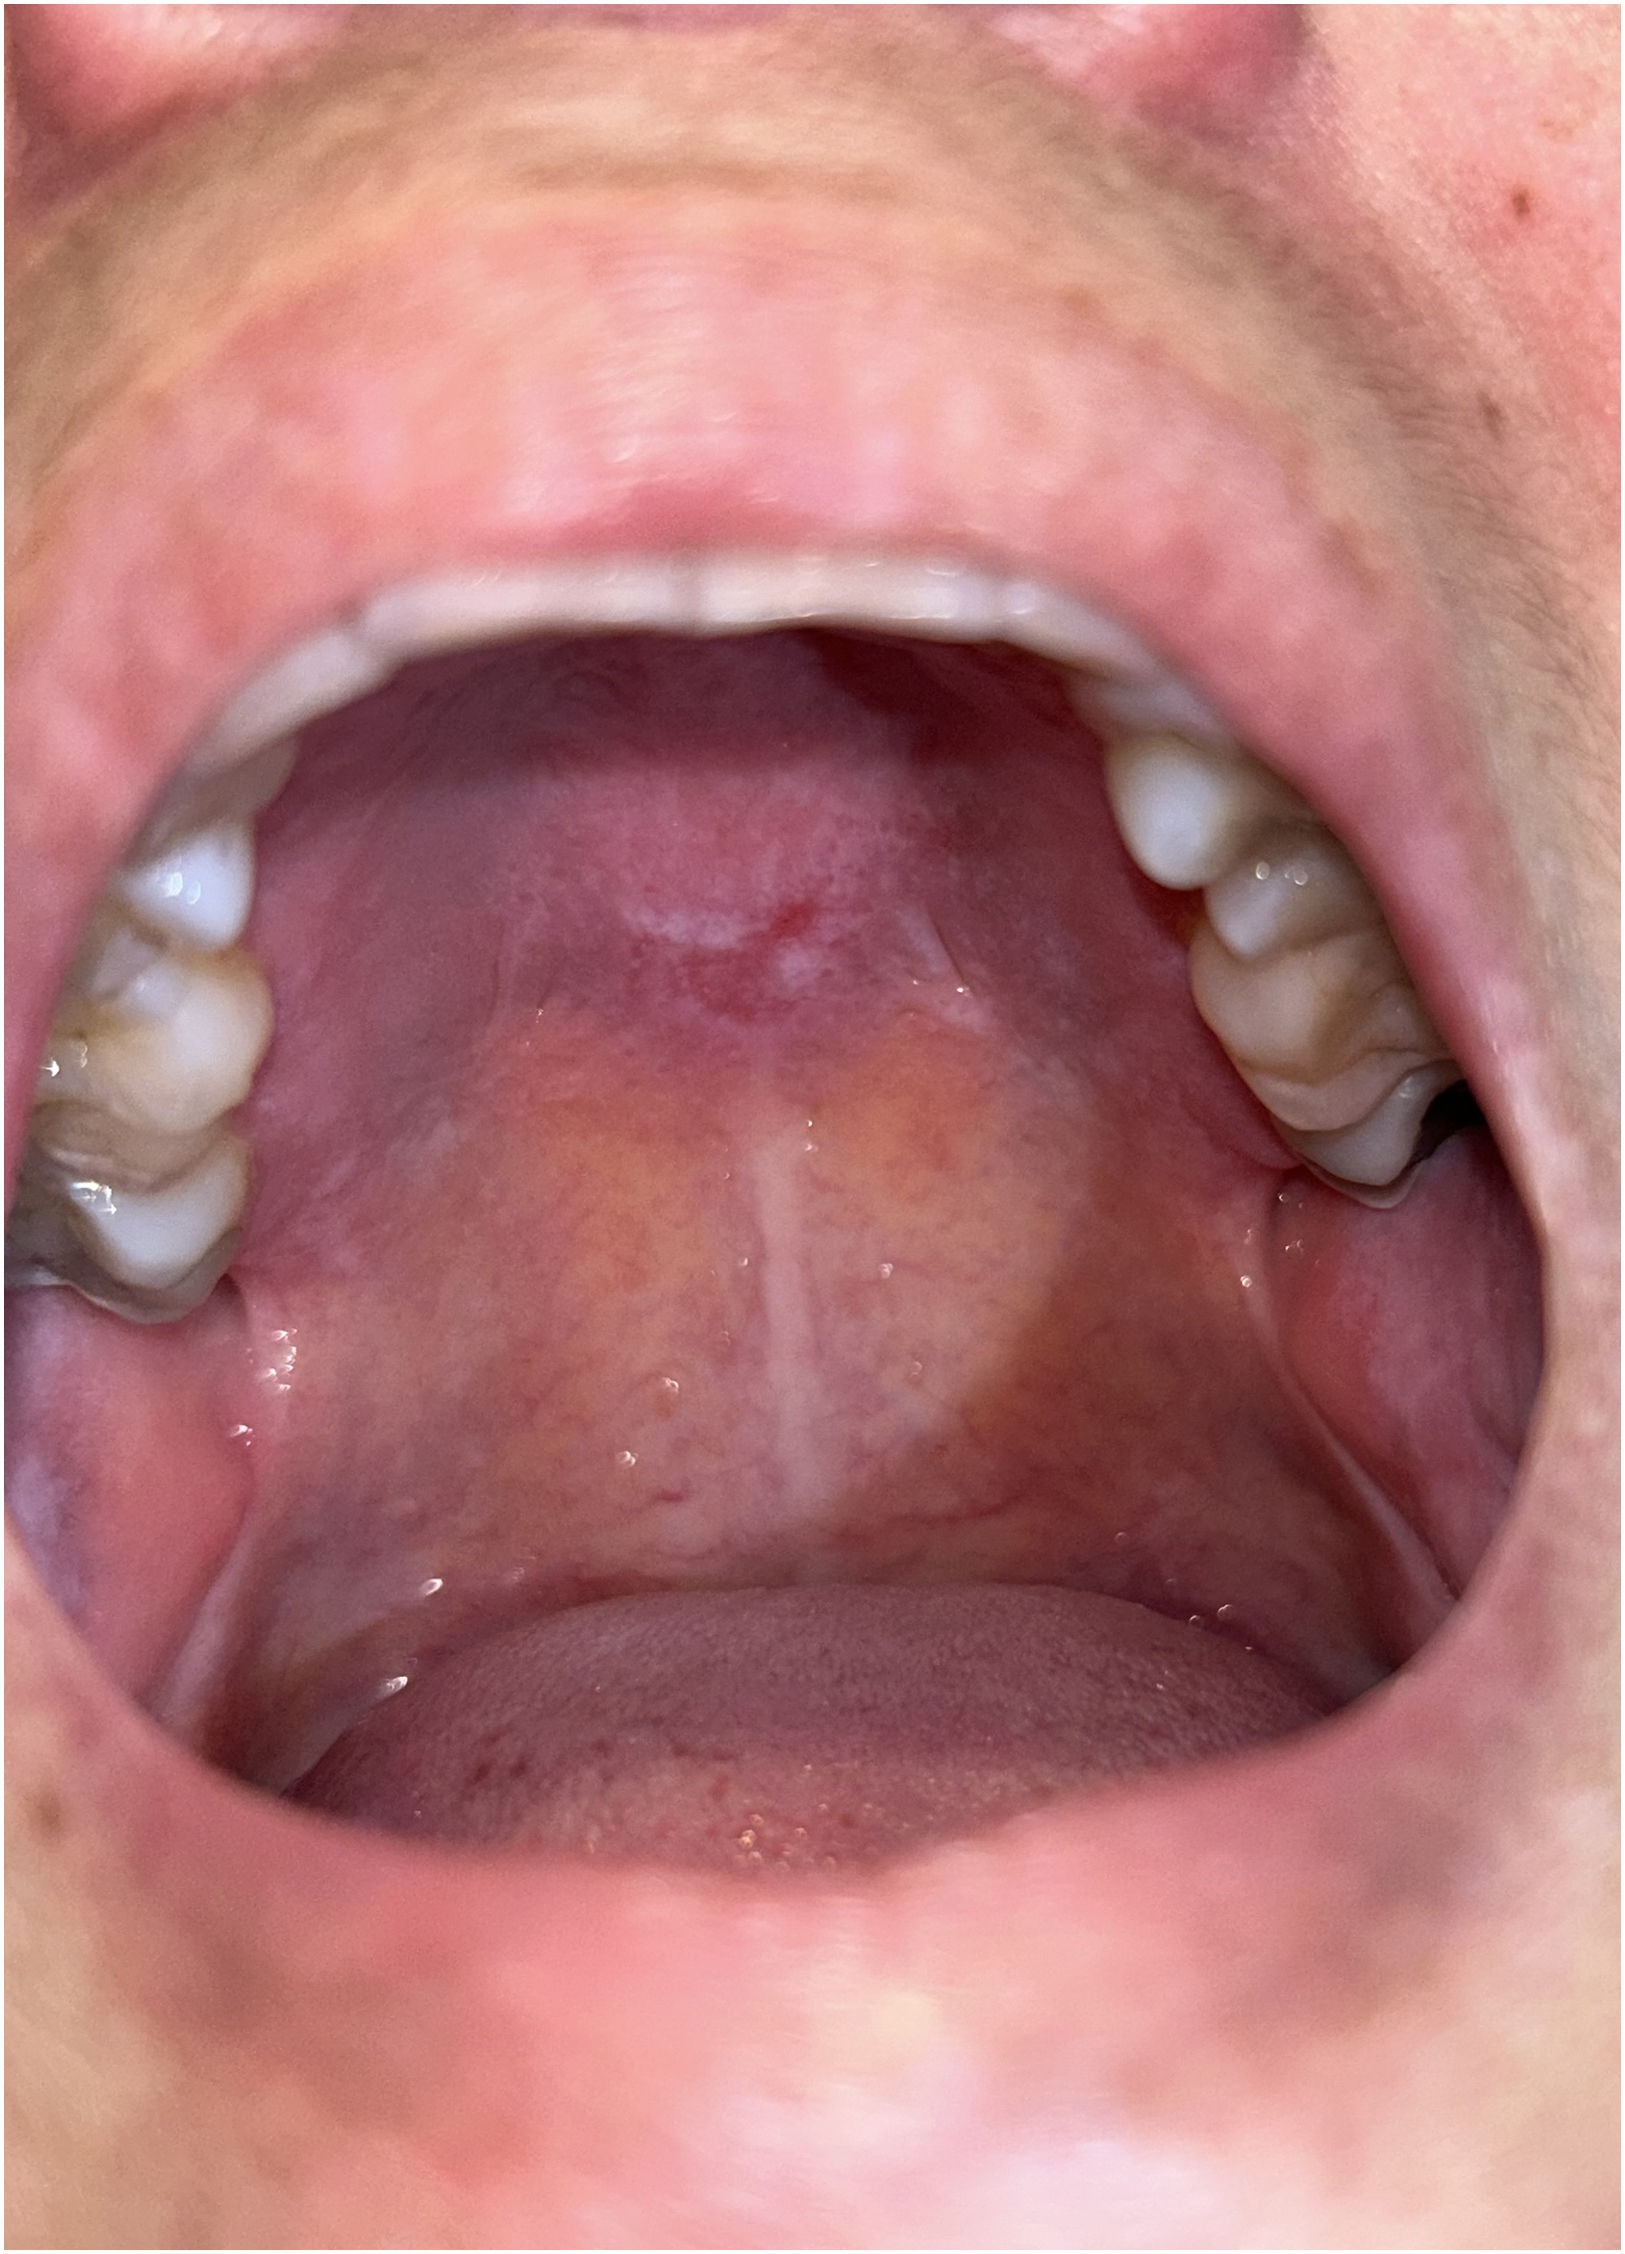

Physical examinationPhysical examination revealed erythematous-violaceous papules over the metacarpophalangeal and proximal and distal interphalangeal joints of both hands (Fig. 1), as well as on the elbows and knees. Dilated capillaries and periungual erythema were also observed, together with an ill-defined hyperpigmented plaque on the upper chest. Examination of the oral cavity showed an oval erythematous macule with well-demarcated whitish areas located on the midline of the hard palate (Fig. 2).

CommentThe palatal ovoid patch is a very uncommon sign of dermatomyositis that appears as a well-demarcated, nonulcerative erythematous macule on the posterior hard palate.1 This mucosal lesion was first described in 2016 by Bernet et al., who reported its presence in 18 of 45 patients (40%) and found that it was significantly associated with anti-TIF1γ antibodies and strongly associated with internal malignancy.2 Since then, three additional articles addressing this finding have been published in the literature, summarized below.

In contrast with previous reports, in our case the presence of a palatal ovoid patch was not associated with malignancy or with the TIF1γ immunophenotype but rather with another antibody, anti-Mi-2b, an association not previously described to our knowledge in the literature. This antibody is associated with a classic dermatomyositis phenotype, a good response to treatment, and a low association with malignancy or interstitial lung disease.6